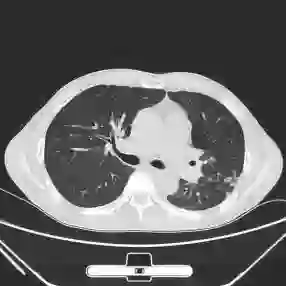

This paper proposes applying a novel deep-learning model, TBDLNet, to recognize CT images to classify multidrug-resistant and drug-sensitive tuberculosis automatically. The pre-trained ResNet50 is selected to extract features. Three randomized neural networks are used to alleviate the overfitting problem. The ensemble of three RNNs is applied to boost the robustness via majority voting. The proposed model is evaluated by five-fold cross-validation. Five indexes are selected in this paper, which are accuracy, sensitivity, precision, F1-score, and specificity. The TBDLNet achieves 0.9822 accuracy, 0.9815 specificity, 0.9823 precision, 0.9829 sensitivity, and 0.9826 F1-score, respectively. The TBDLNet is suitable for classifying multidrug-resistant tuberculosis and drug-sensitive tuberculosis. It can detect multidrug-resistant pulmonary tuberculosis as early as possible, which helps to adjust the treatment plan in time and improve the treatment effect.